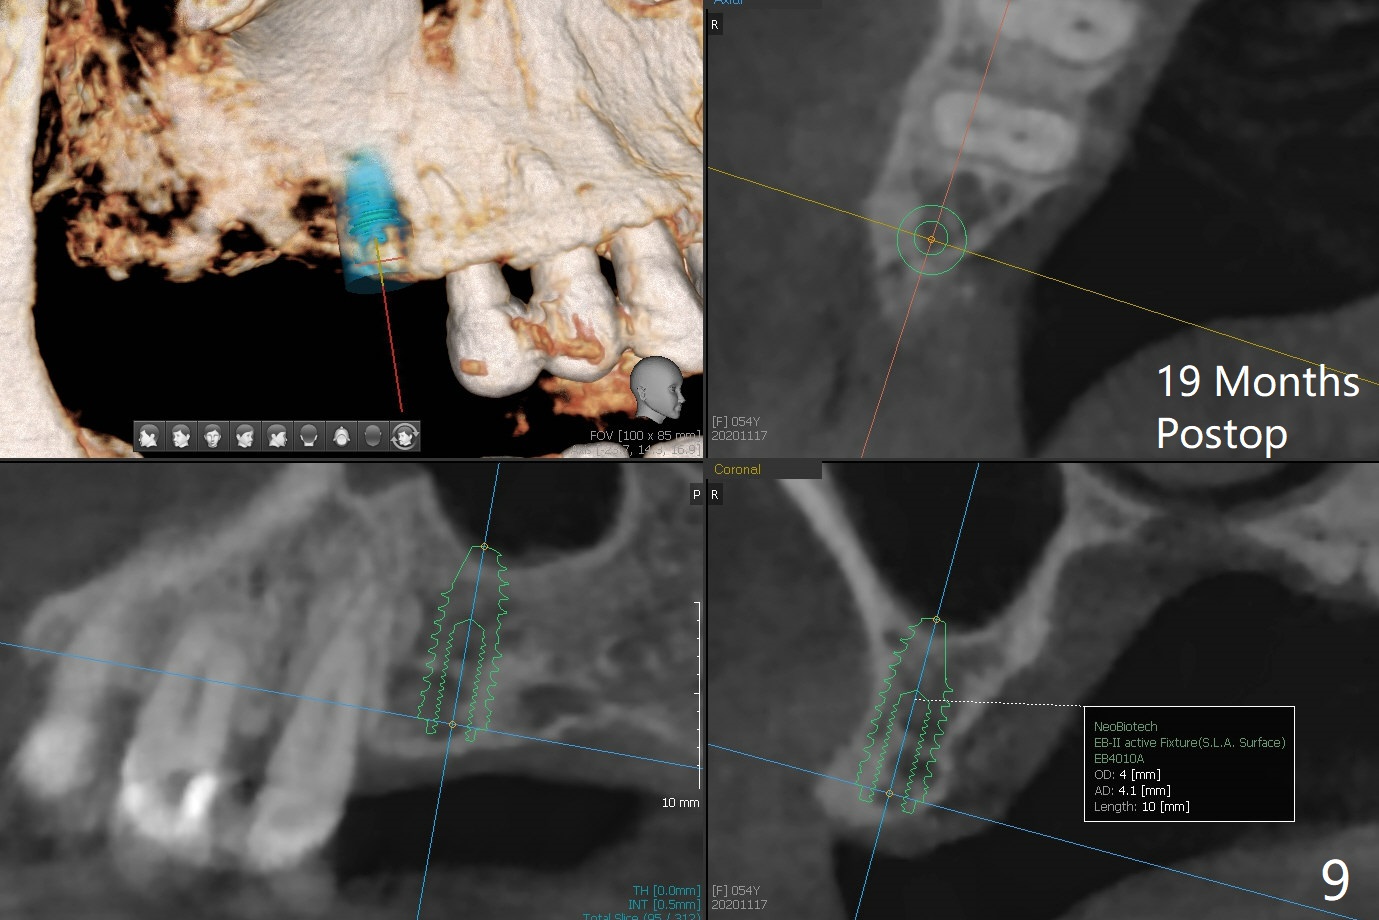

A 53-year-old woman wants to extract the tooth #3 with recurrent apical periodontitis (Fig.1). Socket preservation is conducted (Fig.2). The tooth is terminal in the arch and difficult to keep periodontal or acrylic dressing in place. To overcome the situation, a prefabricated space maintenance is placed without cementation because of its inherent fitness (Fig.3). Periodontal dressing (Fig.4 D) appears to be retained in place. The spacer is lost prematurely due to no cement, but the wound appears to be healing 13 days postop (Fig.5,6). The socket heals 3 months postop (Fig.7,8). However the ridge is narrow 19 months postop (Fig.9, as compared to that of the tooth #14 (Fig.10)).